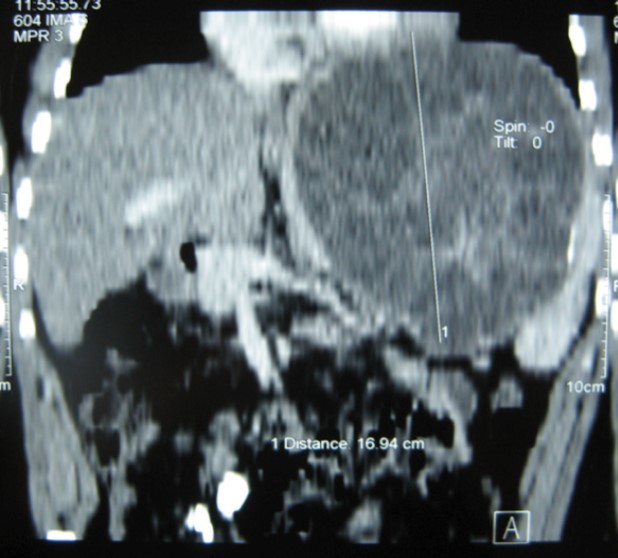

A 17-year-old young man admitted to our department with the complaint of abdominal pain localized in the left upper quadrant for the last 3 months. His physical examination revealed a splenomegaly. Immunoblot assay for Echinococcus was positive. His laboratory tests showed normal results of the serum and urine examinations, No eosinophilia was found. Chest X-ray revealed no pathological signs. An abdominal ultrasonography showed a 20 cm multivesicular cystic mass of spleen (figure 1). Contrast enhanced CT scans detected a huge single 20×16×18cm cystic mass located in the spleen. It had well-defined borders and contained multiple, round, daughter cysts in the periphery of the lesion with calcification (Figure 2, Figure 3, Figure 4). The patient underwent a laparotomy. A large splenic cystic mass was identified, attached to diaphragm, and tail of the pancreas (figure 5). The abdomen was packed with 10% hypertonic saline soaked pads in order to protect peritoneal soilage. A partial cystectomy without splenectomy was performed. Histologic examination of the specimen resection showed an echinococcal organism residing within the hydatid cyst . The patient was discharged after 4 postoperative days. 600 mg per a day of Albendazole therapy was instaured postoperatively and continued for 6 months. Two years after surgery the patient is well with disease free.

Figure 3.CT showing a huge single 20×16×18cm cystic mass located in the spleen

CT showing a huge single 20×16×18cm cystic mass located in the spleen